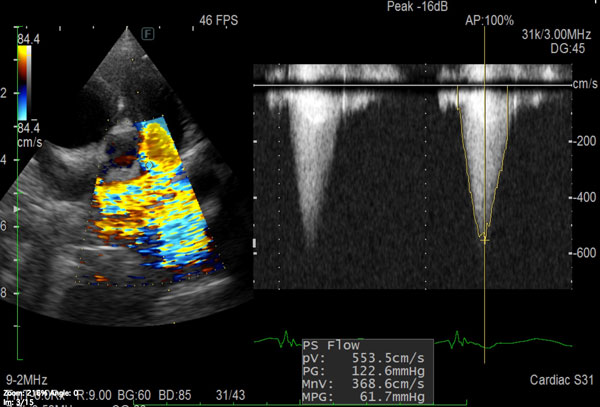

• 循環器疾患(インターベンションによる治療を含む)

手術紹介

肺動脈狭窄症